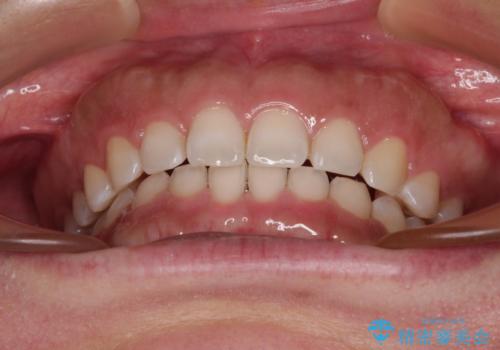

- 顎が疲れるほどのディープバイトを気にして来院された患者様です。

手前に傾斜している奥歯を直立させながら、歯列全体の平面を均一に整えることでディープバイトを改善していくこととしました。

ディープバイトが改善されたことで、食いしばりしかできなかった状態からスムーズな歯ぎしりができるようになりました。